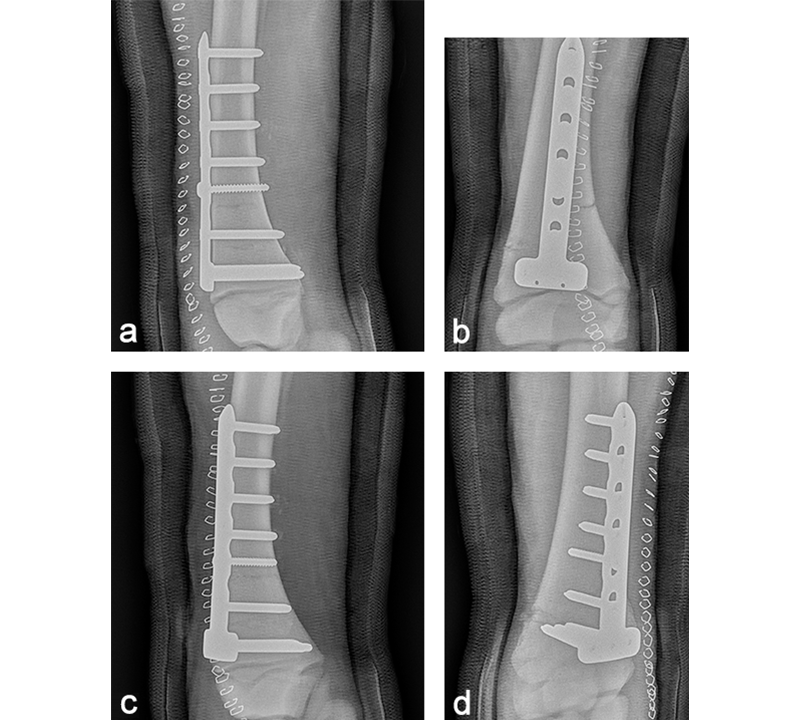

The foal was anesthetized and placed in dorsal recumbency. The left forelimb was placed in extension, clipped, prepared, and draped for aseptic surgery. A cranial approach to the distal aspect of the radius was made. The fracture was reduced, and a 6-hole LCP Equine T-Plate 4.5 was placed beneath the extensor carpi radialis (Fig 11). Two 5.0 mm locking screws were placed in the horizontal portion of the plate to engage the distal portion of the radius, just proximal of the distal radial physis. A 4.5 mm cortex screw was then placed into the second hole of the shaft of the plate, to provide interfragmentary compression and compress the plate to the proximal portion of the bone. The remaining holes were filled with 5.0 mm locking screws. The presurgical planning had included placing a second lateral LCP plate, however, the foals physiological status deteriorated. Further fracture fixation was therefore abandoned, and the surgery site was closed. A tube cast was placed from the level of the fetlock to the proximal radius. The foot and pastern were left free to minimize flexor tendon laxity. The foal was placed in sternal recumbency and required 2 hours of assisted ventilation before she started to breath spontaneously. Following surgery, she stood unassisted and was able to ambulate and suckle.

Postoperatively, the foal was noted to have a moderate carpus valgus deformity. Radiographic assessment, however, showed that the lateral deviation was not due to malalignment of the fracture. A gradual improvement in the degree of valgus deformity has been seen with growth as the foal has matured (Fig 13). Radiographic healing of the fracture has proceeded quickly with very little callus formation (Fig 14).